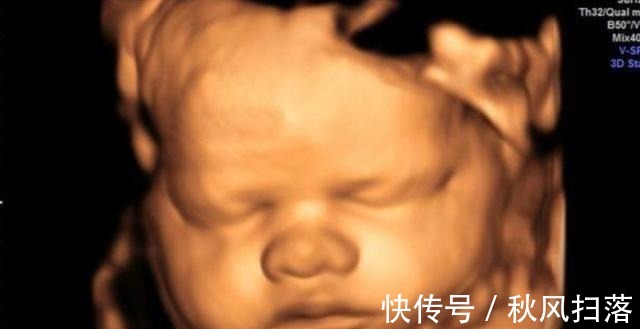

陈女士今年三十三岁,孩子刚刚出生,她非常的开心。别看她如今很坦然,在怀孕期间确实万分小心,对吃的都非常的在意,生怕自己一个不在意对胎儿的身体造成危害。在孕中后期的时候,为了排除更多先天畸形等症状,陈女士在医院做了四维检查。

第一次做检查时,胎儿的脸部、身体都看得非常的清楚,让陈女士感到了很大的安慰。值得一提的是,孩子的一只手伸出了一个手指,非常的可爱。让人没想到的是,第二次检查时,孩子的手指伸出了两根,第三次手指变为了三根,最后一次检查,孩子的手指就变成了四根。